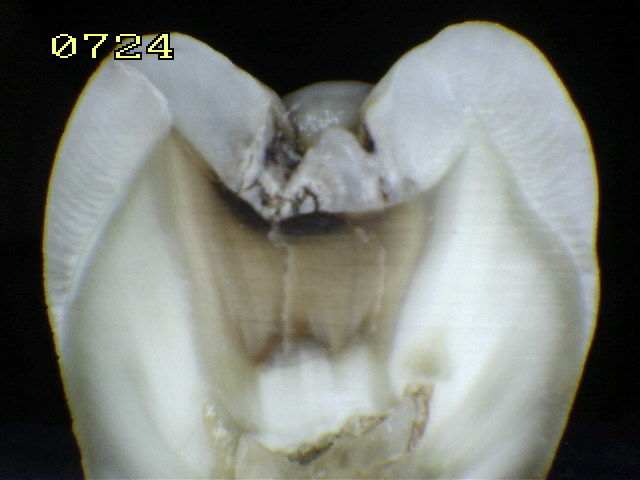

2. CÓDIGO 6

1. Cavidad extensa con paredes y piso en dentina.

1. DIAGNOSTICO DENTAL: CARIES CAVITACIONAL (ACTIVA / NO ACTIVA). Es activa cuando a la exploración clínica con cucharilla el tejido cariado se puede retirar acompañada de otros signos como encía enrojecida y presencia de sangrado, cuando es inactiva vemos que hay dentina reparativa de por medio, esta se ve opaca y no brillante.

1. TRATAMIENTO: Orientación en normas y educación de higiene oral al padre/madre/menor, control de placa, profilaxis, esta lesión puede comprometer la pulpa y consigo debe de realizar un tratamiento pulpar junto con una restauración ya sea en amalgama o composite, si esta lesión no es tan severa se retira la caries posterior a esto se realiza la reconstrucción de la pieza dental o si no hay mucho remanente se recurre a corona de acero en posteriores ó forma plástica en anteriores.